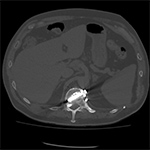

| 70 year-old man with history of L1 and L3 injury and T11-L3 spinal fusion in the 1990's. Recent worsening of chronic lower back pain. Standard radiographs (left two images) show a vertebral body corpectomy cage at T12-L3 with placement of a left lateral side plate at the same levels. There are two proximal screws at T12, one of which enters the spinal canal as shown on subsequent CT (right two images). There are two distal screws at L3, the most distal of which enters the L3-4 disk space (lateral radiograph). |